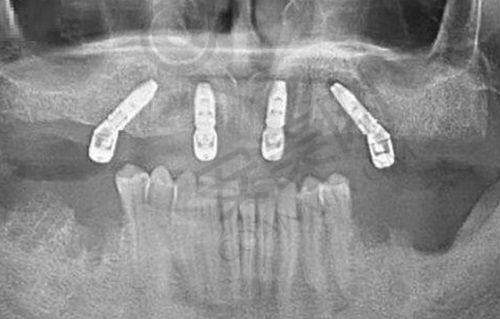

特色项目:除了舌侧保持丝项目,玉溪牙博仕口腔还有特别多特色项目。比如种植牙项目,它可以接诊复杂的疑难病例种植,如allon4种植牙技术,进行4颗种植体就能完成半口种植牙,大大减少了患者的痛苦和治疗成本。